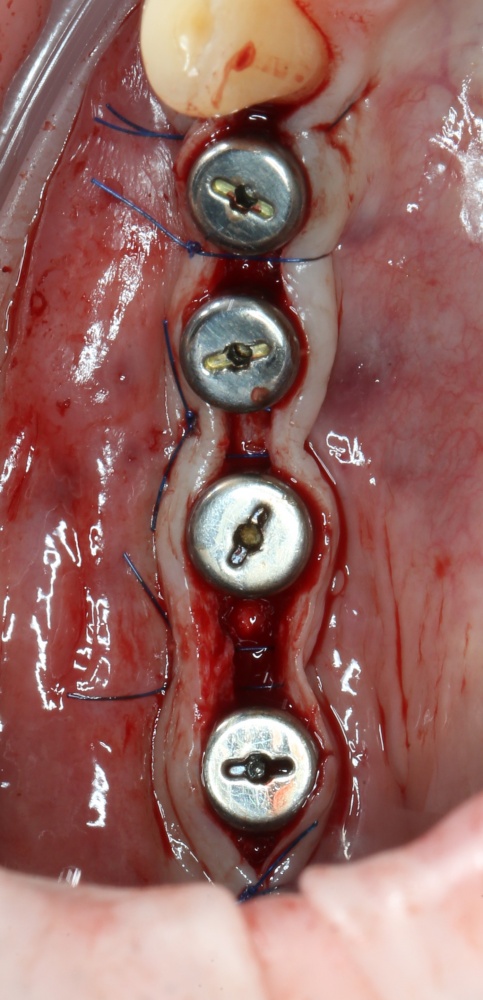

Использование металлоконструкций

Поэтому для реализации остеотомии нам нужны:

— винты. Разных размеров. Для фиксации пластин подойдут самые маленькие — 3-4 мм. Для фиксации самих костных фрагментов или «домкрата» потребуются винты длиннее — 10-12 мм.

— минипластины. Их выпускается огромное количество. Мы используем, в основном, X- и Н-образные минипластины наименьших размеров — с ними легче работать, они легко адаптируются, но есть и минус — иногда гнутся под нагрузкой.

Мы особо не паримся с металлом, предпочитая ритм-энд-блюз или джаз, но если приходится, то нас вполне устраивает отечественный производитель «Коррозия металла» КОНМЕТ:

Во-первых, недорого. Во-вторых, качество, я бы сказал, на уровне.

За редким исключением, минипластины и винты перед имплантацией нужно удалить.

При горизонтальной остеотомии, на мой взгляд, удобнее использовать минипластины. Как я уже отмечал выше, в практике мы используем X- и H-образные минипластины под винты размером 0.9х4мм. Количество металла в разных условиях может быть разным — всё зависит от того, на каком этапе достигается полная неподвижность перемещенного костного фрагмента.